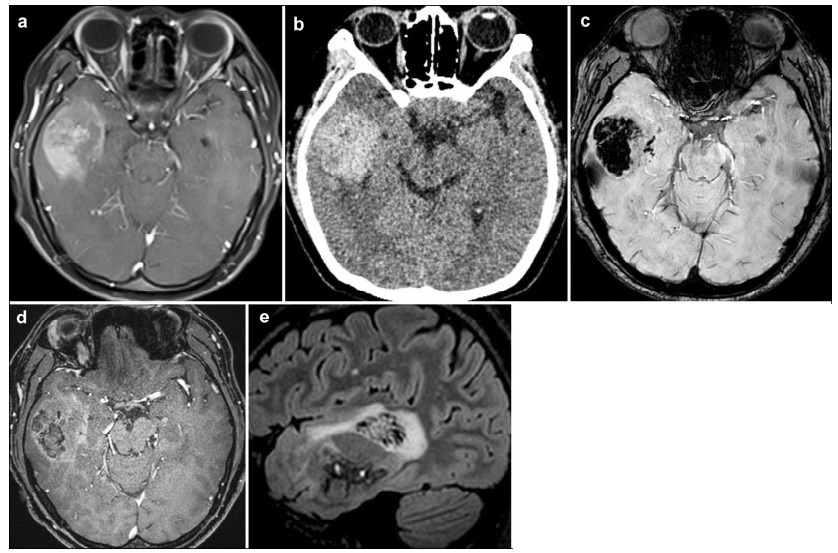

2 Case reportA 34-year-old woman presented with a 9-day history of intermittent dizziness at the Tsinghua University Yuquan Hospital (Beijing, China) in July 2015. No other nervous system deficits were found. Brain MRI (Figure 1a) revealed a 52 mm × 51 mm × 48 mm lesion on the right temporal lobe and showed non-obvious edema and slightly heterogeneous contrast enhancement without centrally necrotic regions. On the other hand, brain computed tomography (CT) (Figure 1b) revealed a hemorrhage on the right temporal lobe. High-resolution susceptibility weighted imaging (SWI) (Figure 1c) showed a hypointensity lesion. Simultaneous noncontrast angiography and intraplaque hemorrhage (SNAP) imaging (Figure 1d) showed that the lesion was rich in vasculature. T2-weighted inversion recovery based sequence for CSF suppression (T2 Flair) imaging also showed that the lesion was rich in small blood vessels (Figure 1e). All these characteristics did not support a diagnosis of glioblastoma. The patient was scheduled to undergo a right frontotemporal craniotomy. During the procedure, the lesion (Figure 2a) had distinct boundaries with reddish brown appearance and was rich in venous vessels. All these results were consistent with the diagnosis of CCM. The lesion was pathologically confirmed as glioblastoma according to the results of histological examination (Figure 2b). The histopathological analysis revealed that the tumor was composed of densely packed cells and showed nuclear and cell pleomorphism. Follow-up MRI performed at 3 months post-surgery showed no evidence of recurrence.

| Figure 2 a The lesion, as observed during the surgical procedure, shows distinct boundaries with reddish brown appearance and is rich in venous vessels. b Histopathological analysis reveals that the tumor is composed of densely packed cells and shows nuclear and cell pleomorphism. The histopathological diagnosis is glioblastom. (Hematoxylin-eosin stain, ×100) |